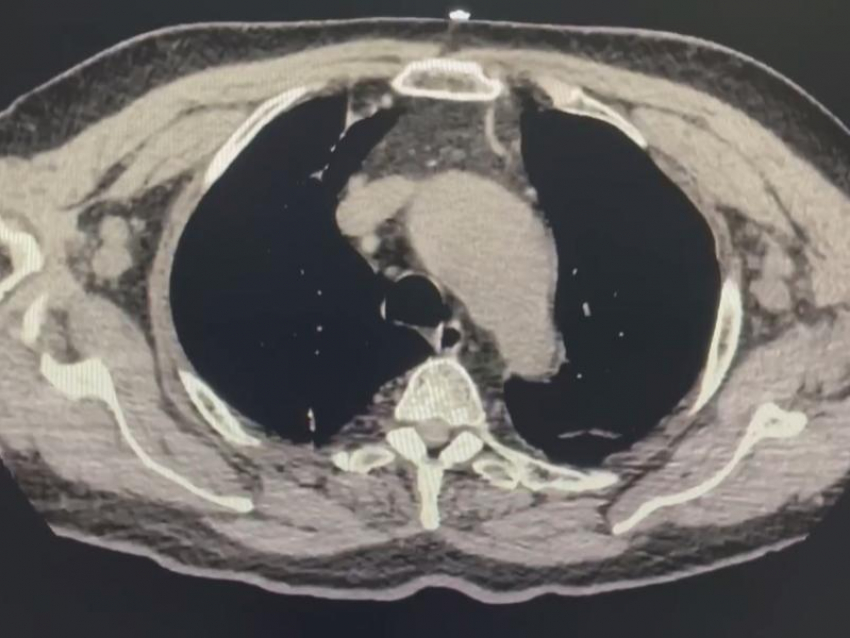

Воронежские врачи провели уникальную операцию, спасшую жизнь 75‑летнему пациенту с расслаивающейся аневризмой дуги аорты – заболеванием, способным привести к мгновенному разрыву сосуда и смерти. Об этом рассказали в министерстве здравоохранения Воронежской области.

Мужчина поступил в БСМП №1 с болями в груди, одышкой и пониженным давлением. После обследований у него выявили экссудативный перикардит и расширение аорты. Позже состояние резко ухудшилось – произошла остановка сердца и дыхания. Кардиологи и реаниматологи провели успешную реанимацию, а затем с коллегами из ВОКБ №1 приняли решение о срочной операции.

Также в минздраве Воронежской области показали кадры компьютерной томографии, на которых видно, что в аорте пациента находится жидкость.